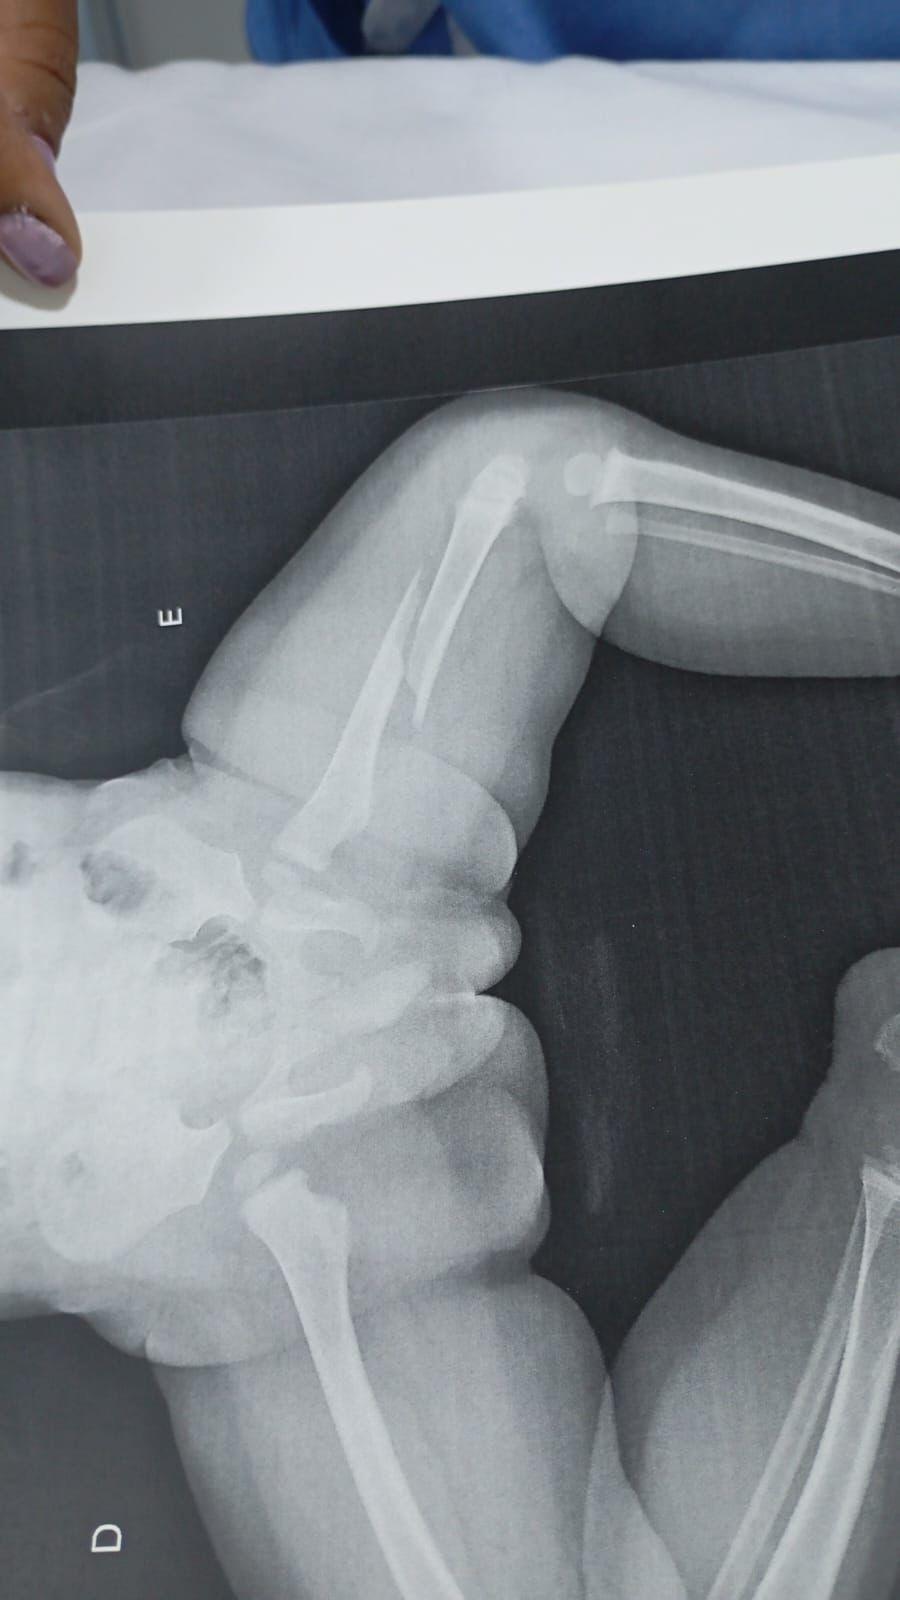

Rosângela Paula Afonso conta como encontrou a criança, que segundo a mãe tinha caído da cama. A suspeita da avó e do pai do bebê é que Benjamin, de um ano e cinco meses, vinha sofrendo agressões: “o médico disse que ele tinha uma fratura antiga no bracinho”. O caso será investigado pela delegacia de Polícia Civil de Paiçandu.

No hospital, os médicos constataram que o fêmur da criança estava fraturado.

Os médicos disseram que a criança também tem uma fratura antiga. [ouça o áudio]